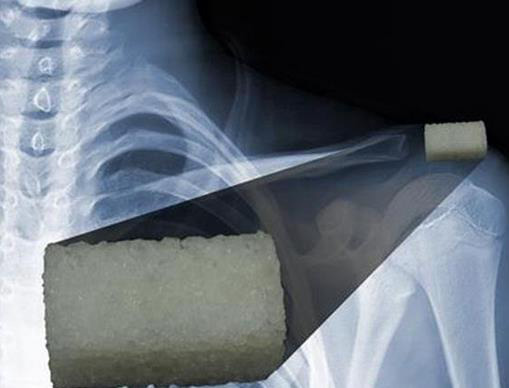

摘要3D打印技術(shù)正迅速成為植入物行業(yè)的一個(gè)重要部分,并通過可量身定制的3D打印植入物在這一領(lǐng)域里掀起一場革命。不過,盡管如此,這個(gè)領(lǐng)域中的最大問題,如何解決人體排異反應(yīng)問題仍然沒有得到根本的解決。幸運(yùn)的是,如今科學(xué)家們在這方面也開始獲得進(jìn)展,比如來自墨西哥普埃布拉自治大學(xué)(BUAP)的一群研究人員已經(jīng)開發(fā)出新合成的3D打印生物材料,可以完全模擬骨骼結(jié)構(gòu)和促進(jìn)骨再生。

據(jù)了解,這一成果是由Efrain Rubio Rosas領(lǐng)導(dǎo)的一群研究人員獲得的。據(jù)他解釋說,這種可生物降解材料是由各種可降解聚合物和羥基磷灰石(通??梢栽谌梭w中找到的一種礦物質(zhì))組成的?!叭梭w骨骼是由有機(jī)材料,如膠原、蛋白和生長因子,和其它無機(jī)材料,如磷酸鈣和羥基磷灰石晶體等,組成的。這些都可以通過合成獲得,當(dāng)它們被用于假體植入物時(shí),可以不被人體拒絕。”他說。

這使得它成為了用于制造植入物和骨組織的小部分替代物很有吸引力的材料?!拔覀兪褂玫氖橇u基磷灰石納米顆粒和可與人體兼容的聚合物,后者會(huì)在體液環(huán)境中降解。不過它會(huì)在足夠長的時(shí)間里提供結(jié)構(gòu)支撐,以便于天然骨骼的生長。”BUAP的研究人員補(bǔ)充說。具體來說,一種羥基磷灰石粉末被用作了骨填料。

最重要的是,這種新型的生物材料可以在孔隙率水平受控的條件下進(jìn)行3D打印,這使得它能夠適用于一系列廣泛的特定應(yīng)用。通過一種特殊的算法,醫(yī)生們可以設(shè)計(jì)三維結(jié)構(gòu)和圖案為每一名病人提供足夠的支持,然后將其3D打印出來。目前科學(xué)家們已經(jīng)為該數(shù)學(xué)模型提交了專利申請。這些研究人員已經(jīng)開始致力于在不久的將來3D打印骨骼。

而現(xiàn)在,他們正字尋求打印出1立方厘米的植入物。除此之外,該校醫(yī)學(xué)系也正準(zhǔn)備驗(yàn)證這一材料的生物相容性。